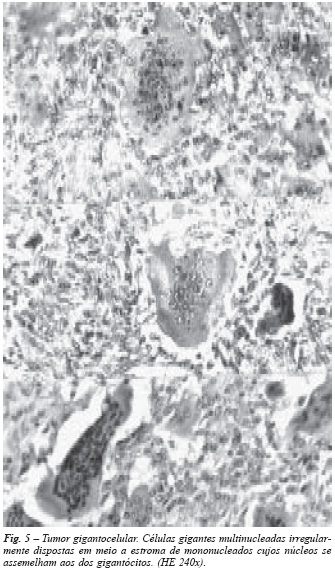

Tumor gigantocelular: neoplasia mais freqüente entre os 20 e 40 anos de idade, de localização epífisaria em ossos longos, menos comum em ossos curtos e chatos. Freqüente nas extremidades proximal da tíbia, distal do fêmur e distal do rádio. Em sua estrutura histológica predominam células gigantes maiores do que o osteoclasto, com numerosos núcleos, às vezes mais de cem, situados em desordem na porção central, formando sincício(5,14). O estroma é constituído por células mononucleadas cujos núcleos se assemelham aos dos gigantócitos (fig. 5). Não raramente existem áreas de fibrose com células xantomatosas, congestão vascular e hemorragias recentes e antigas, estas caracterizadas por aglomerados de macrófagos com hemossiderina.